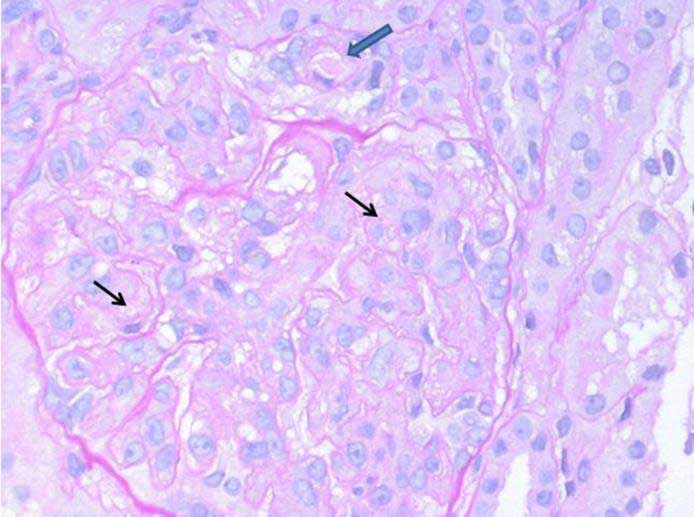

Renal biopsy was done and abnormal findings were seen (see figure). A routine immunofluorescence panel (IgA, IgG, IgM, C1q, C3, and fibrinogen) was substantially negative in glomeruli; C3 complement fraction stained arteriolar walls